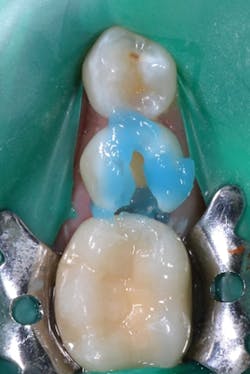

After completing the cavity preparation on tooth No. 29, rubber dam isolation was achieved to create an ideal working field for adhesive dentistry. Because the preparation extended into dentin but had exposed enamel margins, a selective-etch technique was chosen. Caulk 34% phosphoric acid was carefully applied to the enamel margins for 15 seconds (its thicker viscosity helps it stay where placed to prevent dripping onto unwanted areas), followed by water rinsing (figure 2).

Figure 2: The selective-etch technique was used with 34% phosphoric acid applied for 15 seconds.